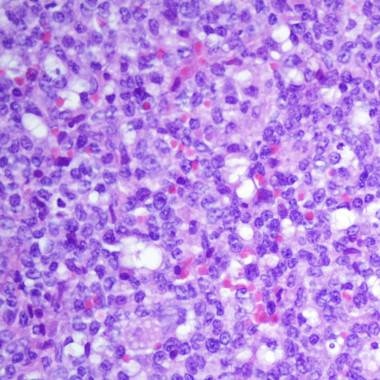

![[Img #51003]](upload/img/periodico/img_51003.jpg)

(Foto: Jose Martin-Subero. Institut d’Investigacions Biomèdiques August Pi i Sunyer (IDIBAPS), Barcelona, Spain)